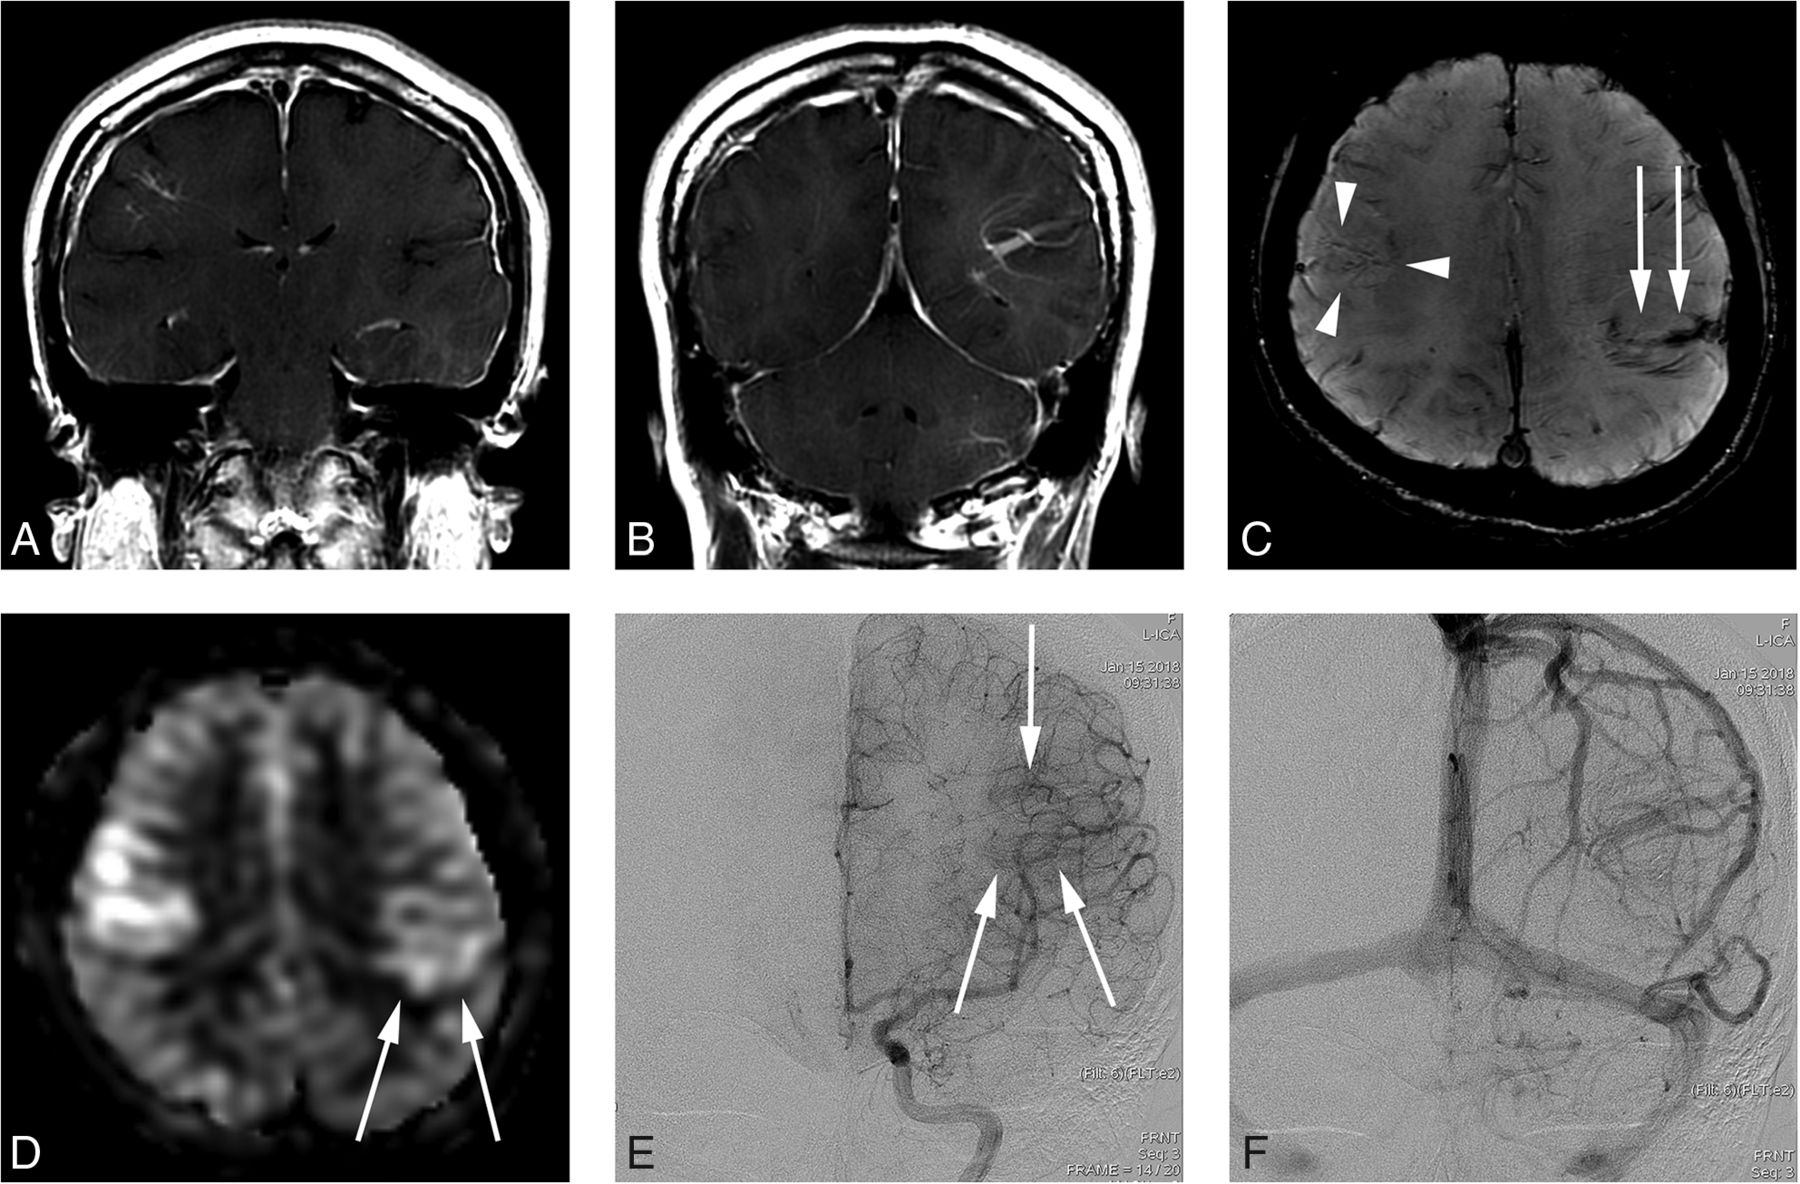

A 29-year-old man presenting with an AVM in the left occipital lobe (case 11). A, Contrast-enhanced T1-weighted axial MR imaging shows a DVA-like lesion in the right frontal lobe. B, SWI shows hypointense signal in the lesion. C, An ASL quantitative CBF image demonstrates no identifiable signal corresponding to the lesion. D, On DSA, the lesion is first visualized in the late venous phase (arrows), as is typically seen in a classic DVA.